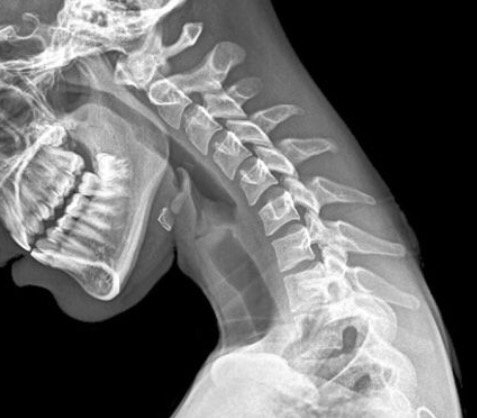

• Och nu… Gamnacke – för vi satt ju aldrig innan och tittade ner i skolböcker?

Läs om din blivande gamnacke/paddnacke här:

http://touch.metro.se/17-arig-flicka-fick-gam-nacke-av-att-smsa/EVHode!izBkhBgcmC1A/